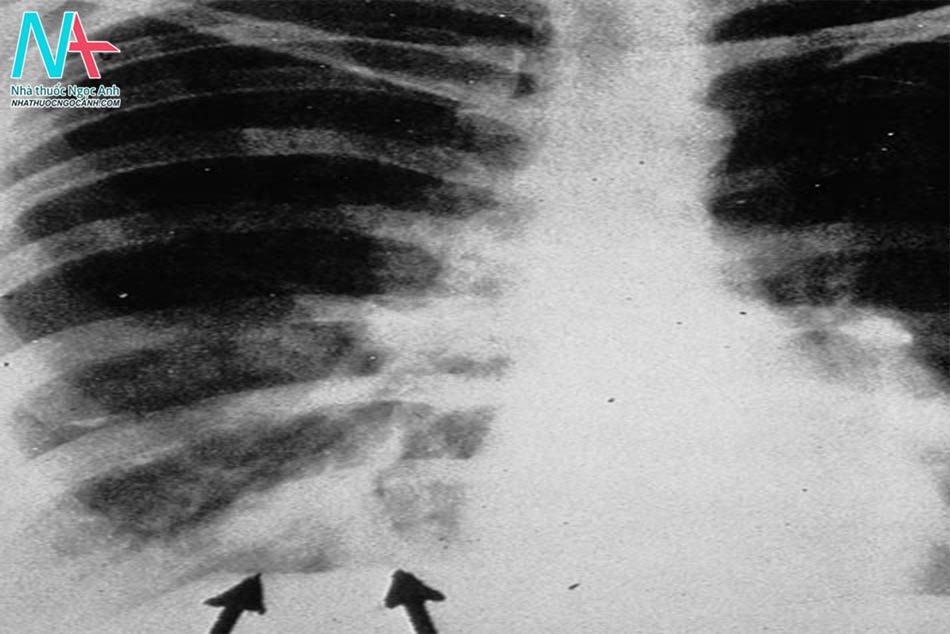

Nam 54 tuổi tới phòng khám do mệt mỏi, ho có đờm với đờm dính dây máu, sụt 7kg vài tháng nay. Ông ta không sốt, đau ngực, ra mồ hôi đêm. 10 năm trước, bệnh nhân đi về từ Việt Nam nơi mà ông ta được điều trị bệnh lao. Ông ta không có tiền sử y tế nào khác. Không hút thuốc hay sử dụng chất cấm nhưng thỉnh thoảng có uống rượu. Thân nhiệt 36.7 độ C, huyết áp 120/80 mmHg, mạch 82 lần/ph. Nghe phổi thấy ran ẩm và ran ngáy ở phổi phải. Creatin huyết tương là 1.1 mg/dL và kết quả phân tích nước tiểu bình thường. Hình ảnh CT ngực như hình bên dưới:

Chẩn đoán nhiều khả năng nhất ở bệnh nhân này?

Đáp án đúng là C: Aspergillus là một loại nấm phổ biến và nhiều người tiếp xúc hàng hít vào trong phổi và trở thành sợi nấm có khả năng gây bệnh 1 có sức đề kháng bình thường (immunocompetency) nhanh chóng nhanh chóng loại bỏ tác nhân gây bệnh và hiếm khi xuất hiện viêm tiến triển nhưng với bệnh nhân suy giảm sức đề kháng như tiền sử mắc bệnh phổi (Lao màng phổi) có thể tiến triển bệnh phổi mãn do Aspergiilus (Chronic pulmonary Aspergillosis-CPA) tại vùng phổi đã tổn thương trước đó. Chẩn đoán được dựa trên sự xuất hiện của cả 3 yếu tố sau:

- Triệu chứng kéo dài trên 3 tháng: Sốt, sụt cân, mệt mỏi, ho, ho máu và/ hoặc khó thở.

- Tổn thương màng phổi chứa mảnh vụn (debris), dịch hoặc bóng nấm (Aspergilloma).

- Kháng thể IgG của Aspergillus trong huyết tương dương tính.

Điều trị phụ thuộc vào triệu chứng và mức độ trầm trọng bệnh, các thuốc chống nấm (Itraconazole, Voriconazole), phẫu thuật (Để ngăn chặn ho máu) và gây thuyên tắc động mạch phế quản (gây ho máu ở tình trạng bệnh nặng) có thể được sử dụng kết hợp hoặc riêng biệt.

Nếu chỉ có bóng nấm thì đôi khi được xem giống như CPA nhưng thường không rõ ràng (chỉ có ho nhẹ thoáng qua hoặc ho máu) mà không có triệu chứng toàn thân. Bệnh nhân thường mắc CPA điển hình nhiều hơn là chỉ có mỗi Aspergilloma.

Tổng kết: Bệnh phổi mãn do aspergillosis biểu hiện bằng sụt cân, ho, ho máu, mệt mỏi kéo dài >3 tháng ở bệnh nhân có tiền sử bệnh phổi. Hình ảnh thường thấy tổn thương phổi tại thành kèm hoặc không kèm Aspergilloma. Chẩn đoán dựa trên IgG Aspergillosis trong huyết thanh dương tính kèm dấu hiệu lâm sàng và chẩn đoán hình ảnh.